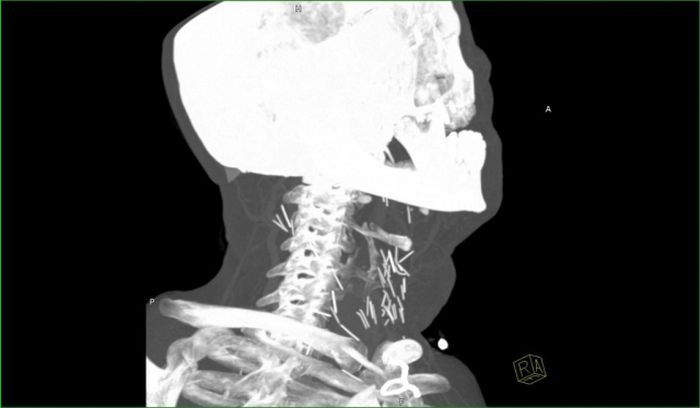

Рентген показал, что у чувака в шее огромное количество иголок.

Оказалось, что товарищ - нарк со стажем и все эти иглы остались в шее после неаккуратных инъекций.